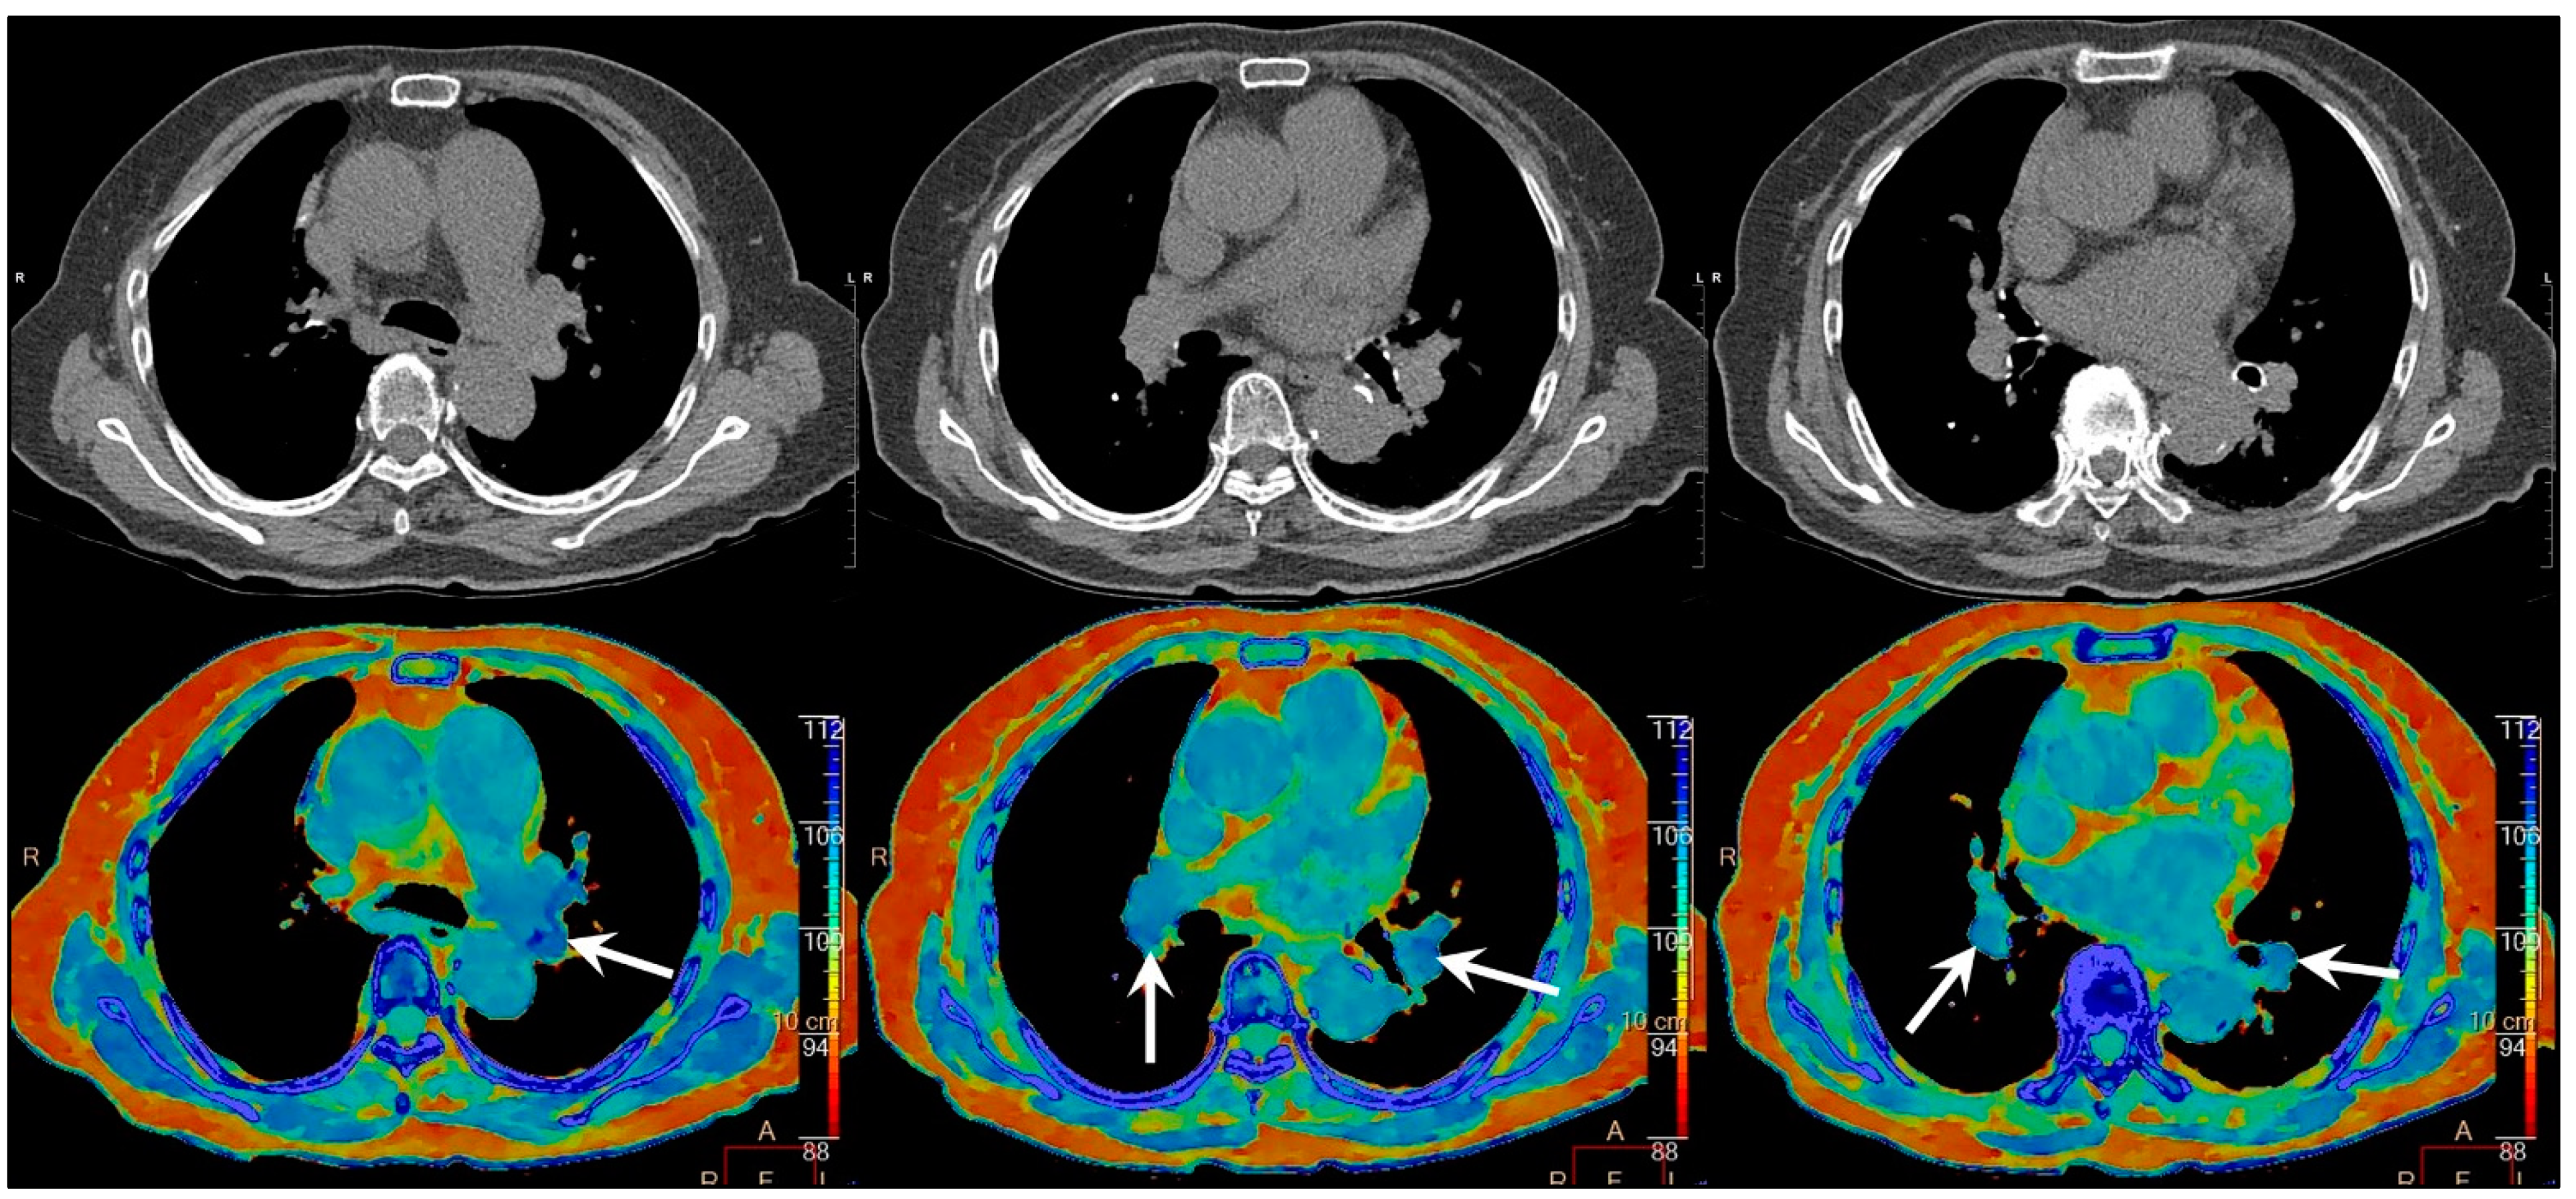

2. Case Report

3. Discussion